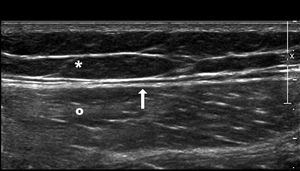

The most common ultrasound characteristic was one fusiform, anechoic collection. All of the acute collections, except for one, were anechoic, and only one collection was chronic (Figs. 1 and 2).

Normal superficial anatomy of the outer side of the thigh. Subcutaneous fat tissue (asterisk), deep fascia (arrow), and vastus lateralis muscle (circle). In the MLL, one trauma—usually a high-energy trauma, causes tangential shear that gives rise to a sudden separation of the skin and the subcutaneous cell tissue of the underlying fascia creating a cavity that ends up filling up with blood and lymph. MLL: Morel-Lavallée lesion.